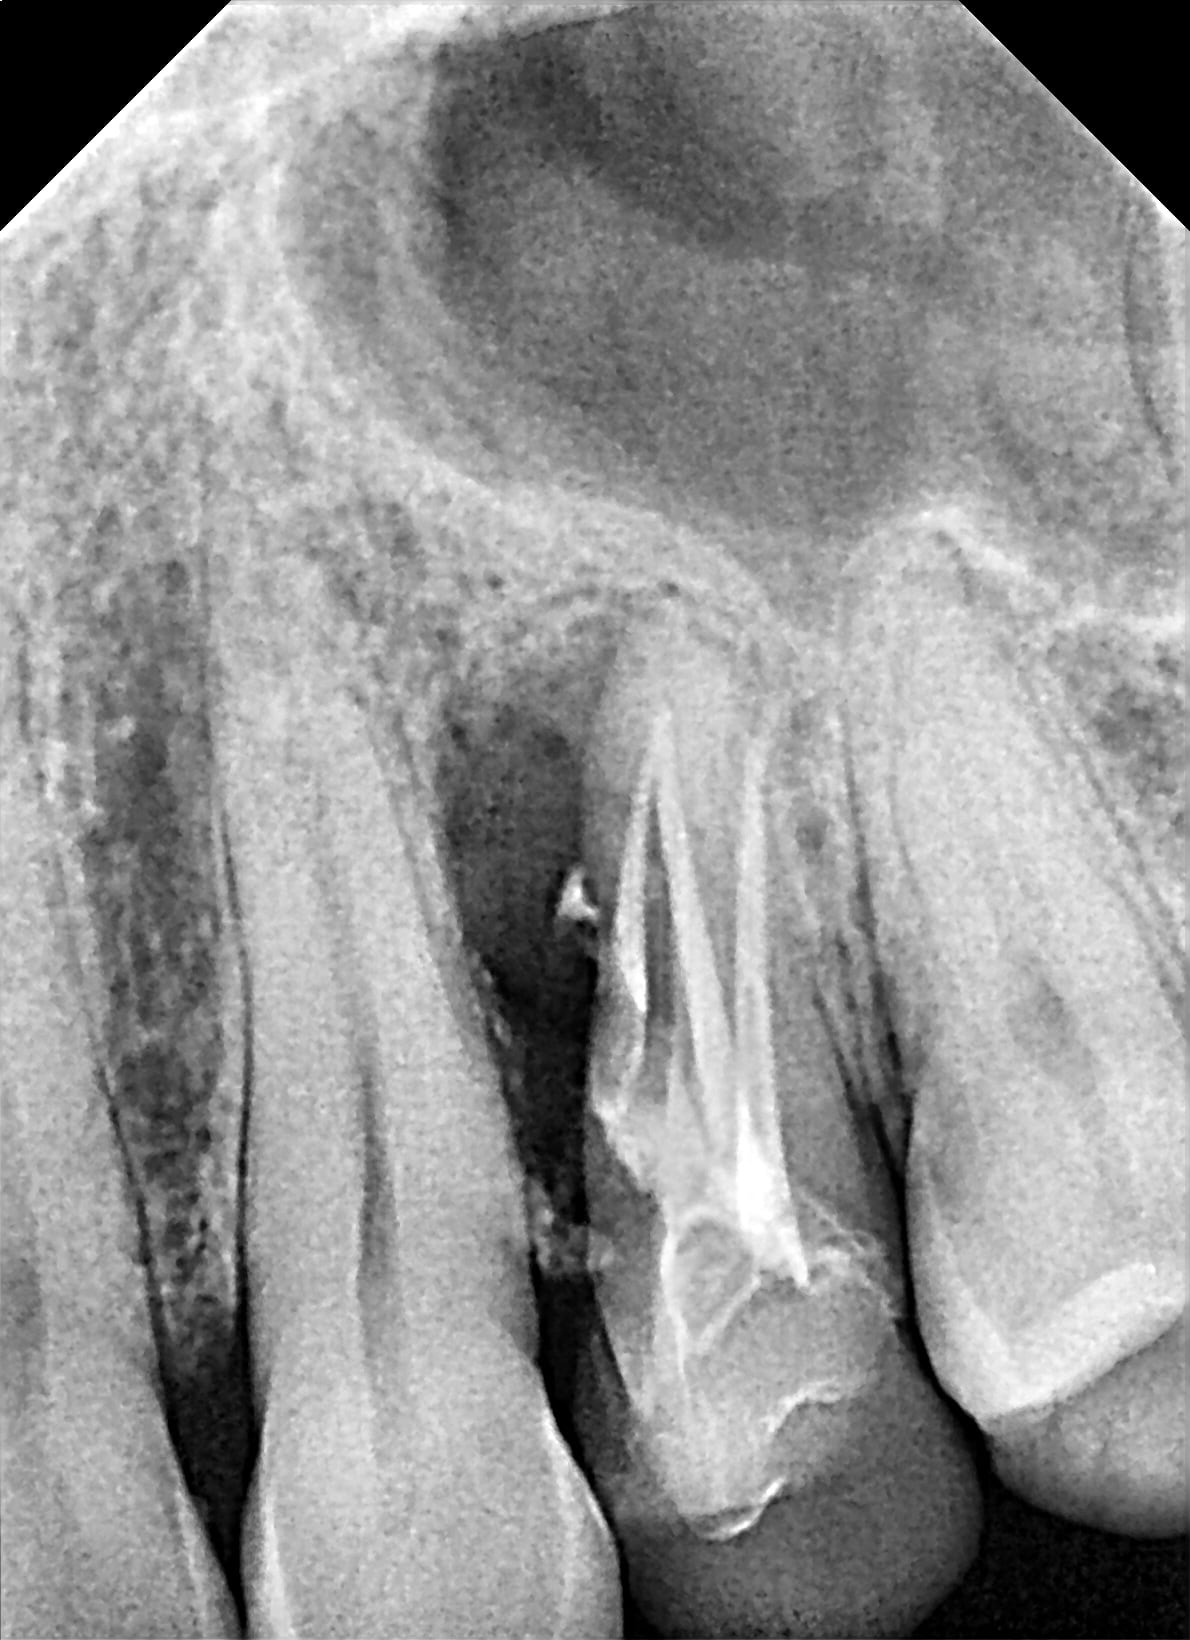

CasKiPu N°1:

Une 24 qui c'est fait mesialo-troué un troisième virtuel il y a un environ an chez un patient en pleine forme. Résine une dent ($$$) ou cobaye ? il dit cobaye :)

stabilité nickel , maxi patate en mesial, exo difficile car racine en forme de boursouflure coalesco-divergente.

Je dilate, ça sort.

visuellement c'est la merde:

- un cône de gutta

- une coulure de ce qui semble être un ciment composite

- un bouchon de MTA-like.

Coup de bistrac sur la racine, je gratoulle une couche de MTA et vu la coulure de compo je curète léger (ce que je ne fait jamais d'habitude) voir si il n'y aurai pas du rab.

J'enfourne ensuite au plus vite, deux point de superbond sur les adjacente (alvéole dilatée), un doliprane, ordo pour un cierge à la grotte et adishatz.